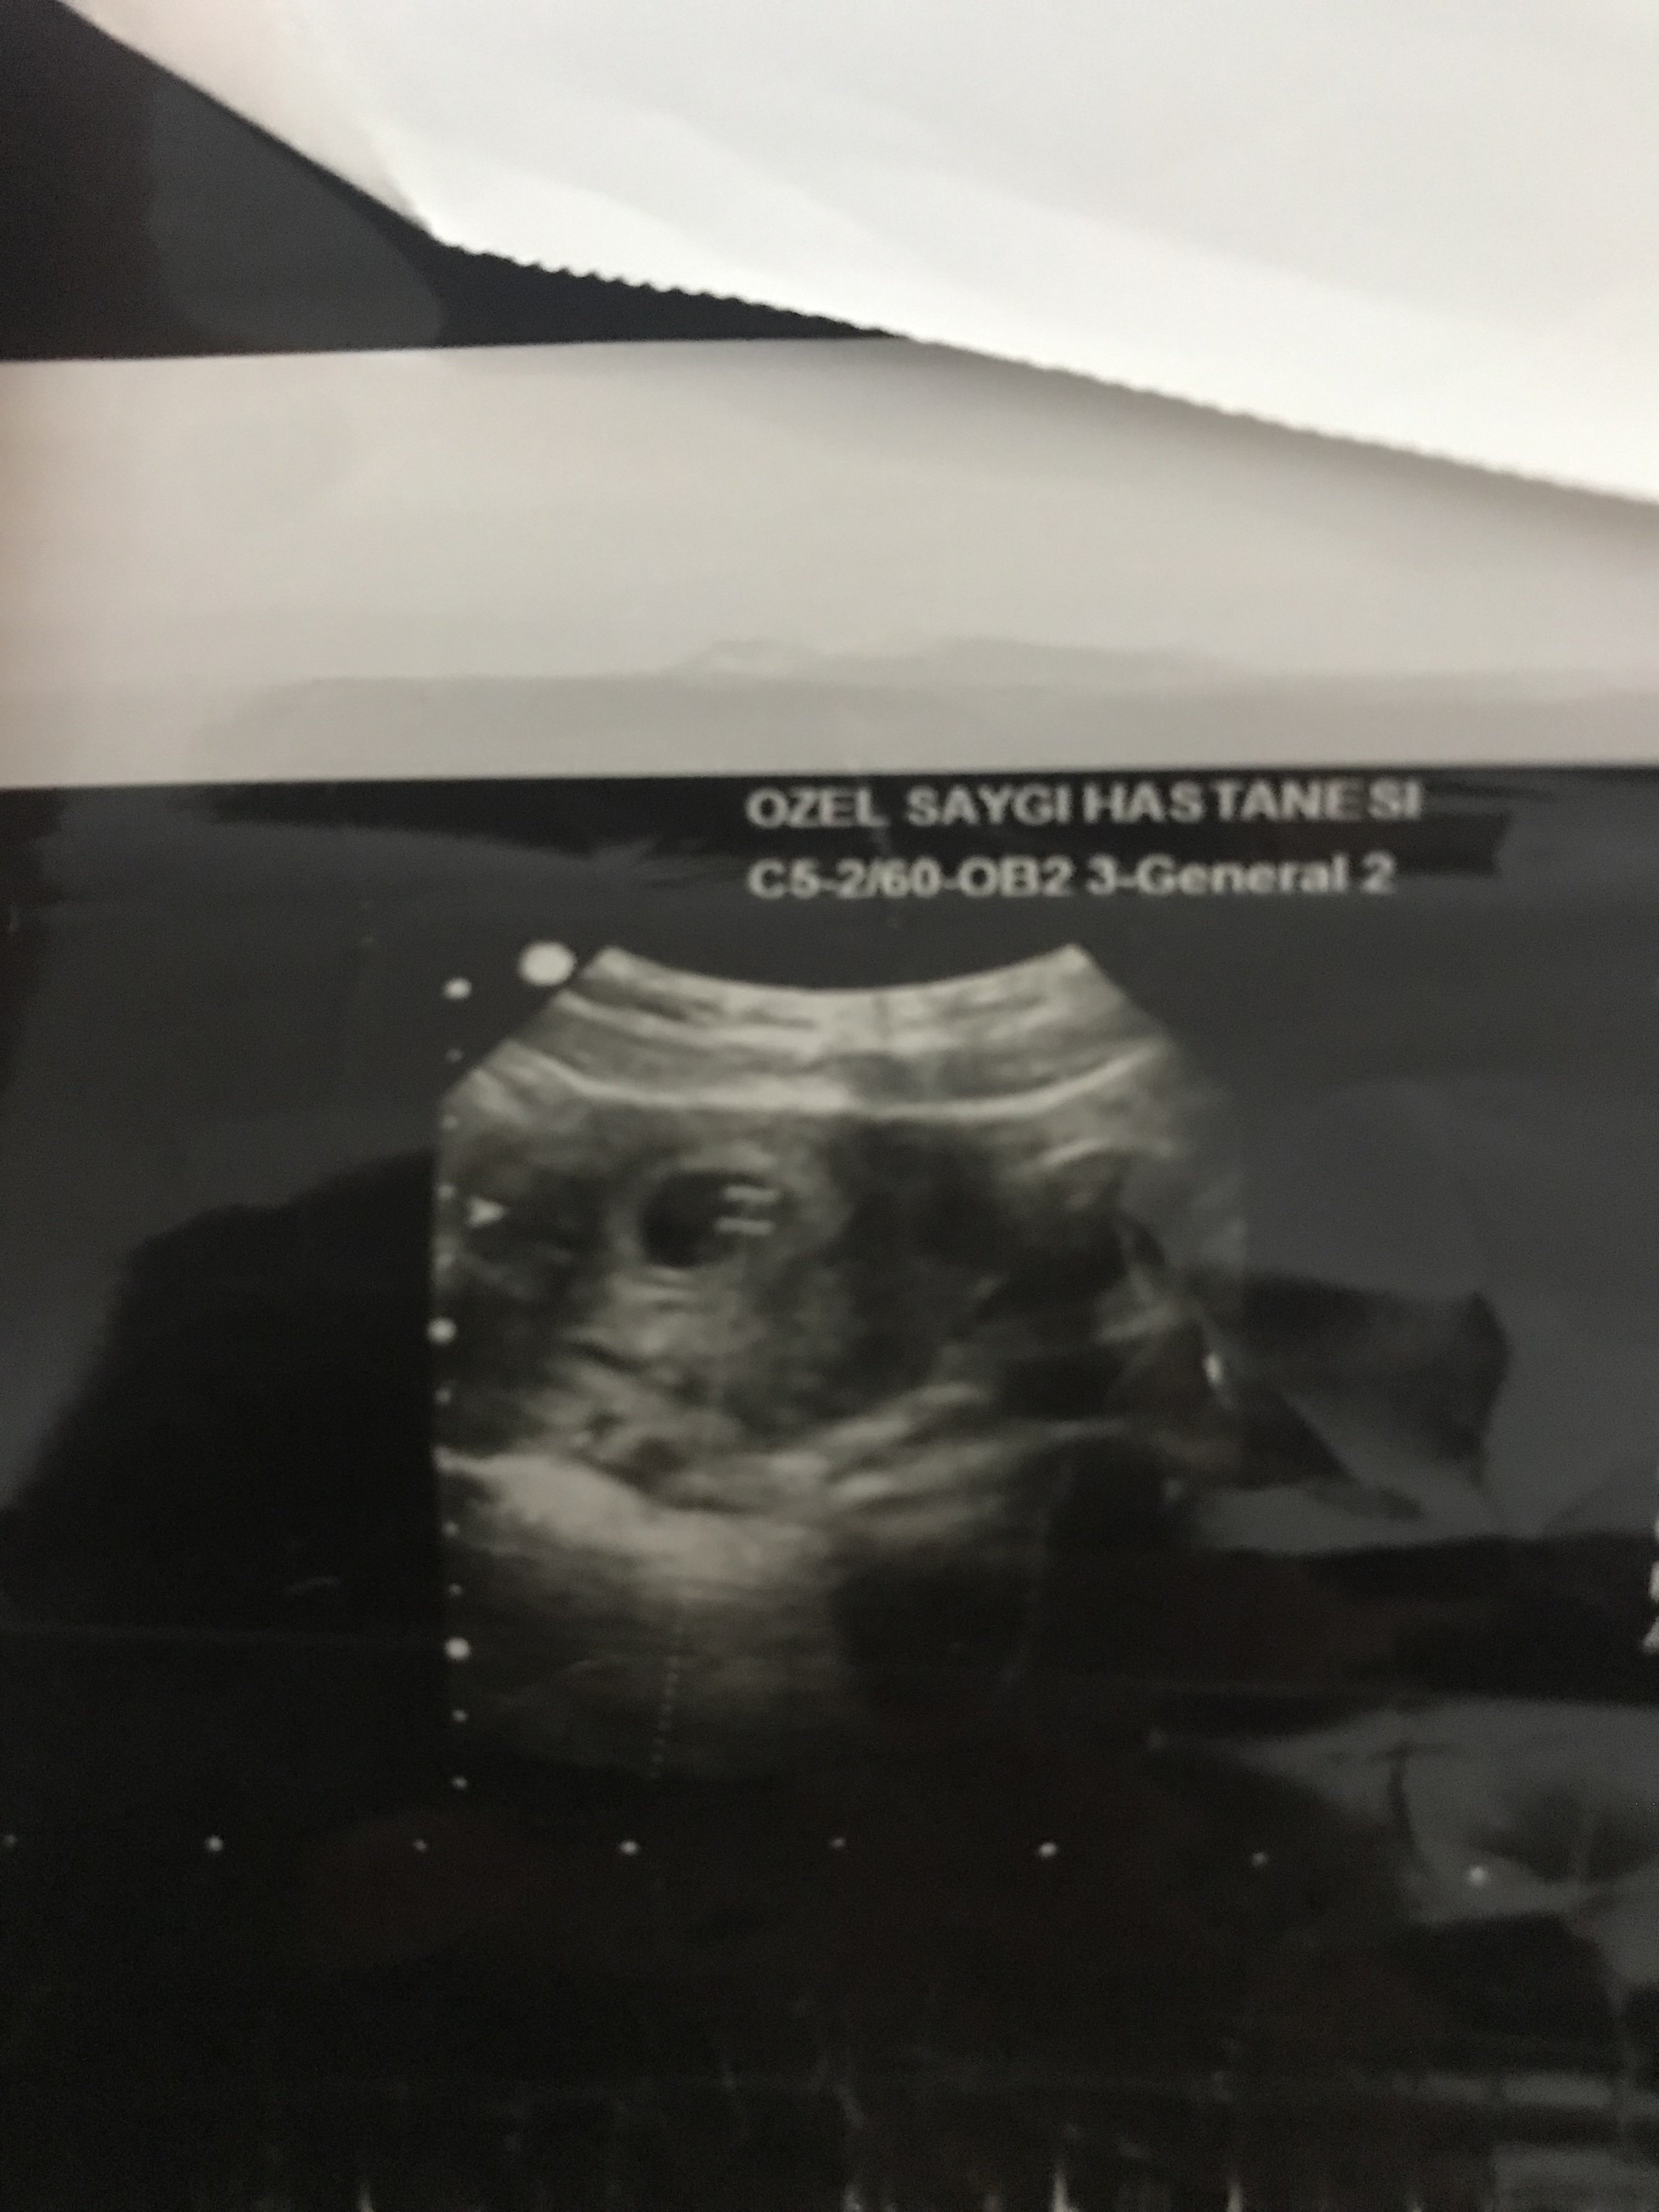

Merhaba .Bunlarda 6+4 günlük usg fotolarım.Ramzi teorisine göre de yorum yapabilir misiniz

• 53B4F22E-2F0D-4966-8F82-7EA9BD134A39.jpeg

53B4F22E-2F0D-4966-8F82-7EA9BD134A39.jpeg

1,2 MB · Görüntüleme: 319

Selamlar, bu yuvarlak kese olan bölümü yakın atar mısınız tam anlamı ile yorum yapamıyoruz görmediğimiz için